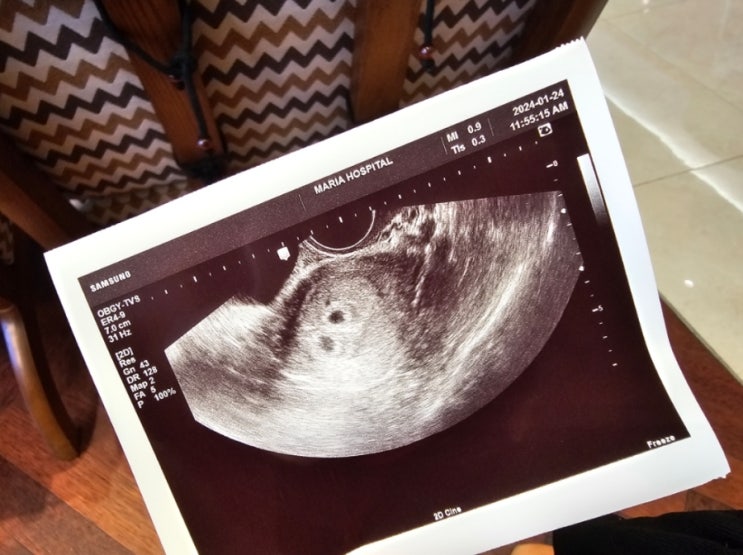

1월 24일 쌍둥이 첫 초음파사진 찍은 날

감동받은 날이라 기록하고 싶었는데 육아하느라 저장해놓고 지나갔다ㅋ 시험관 시술의 경우 5일~일주일이면...